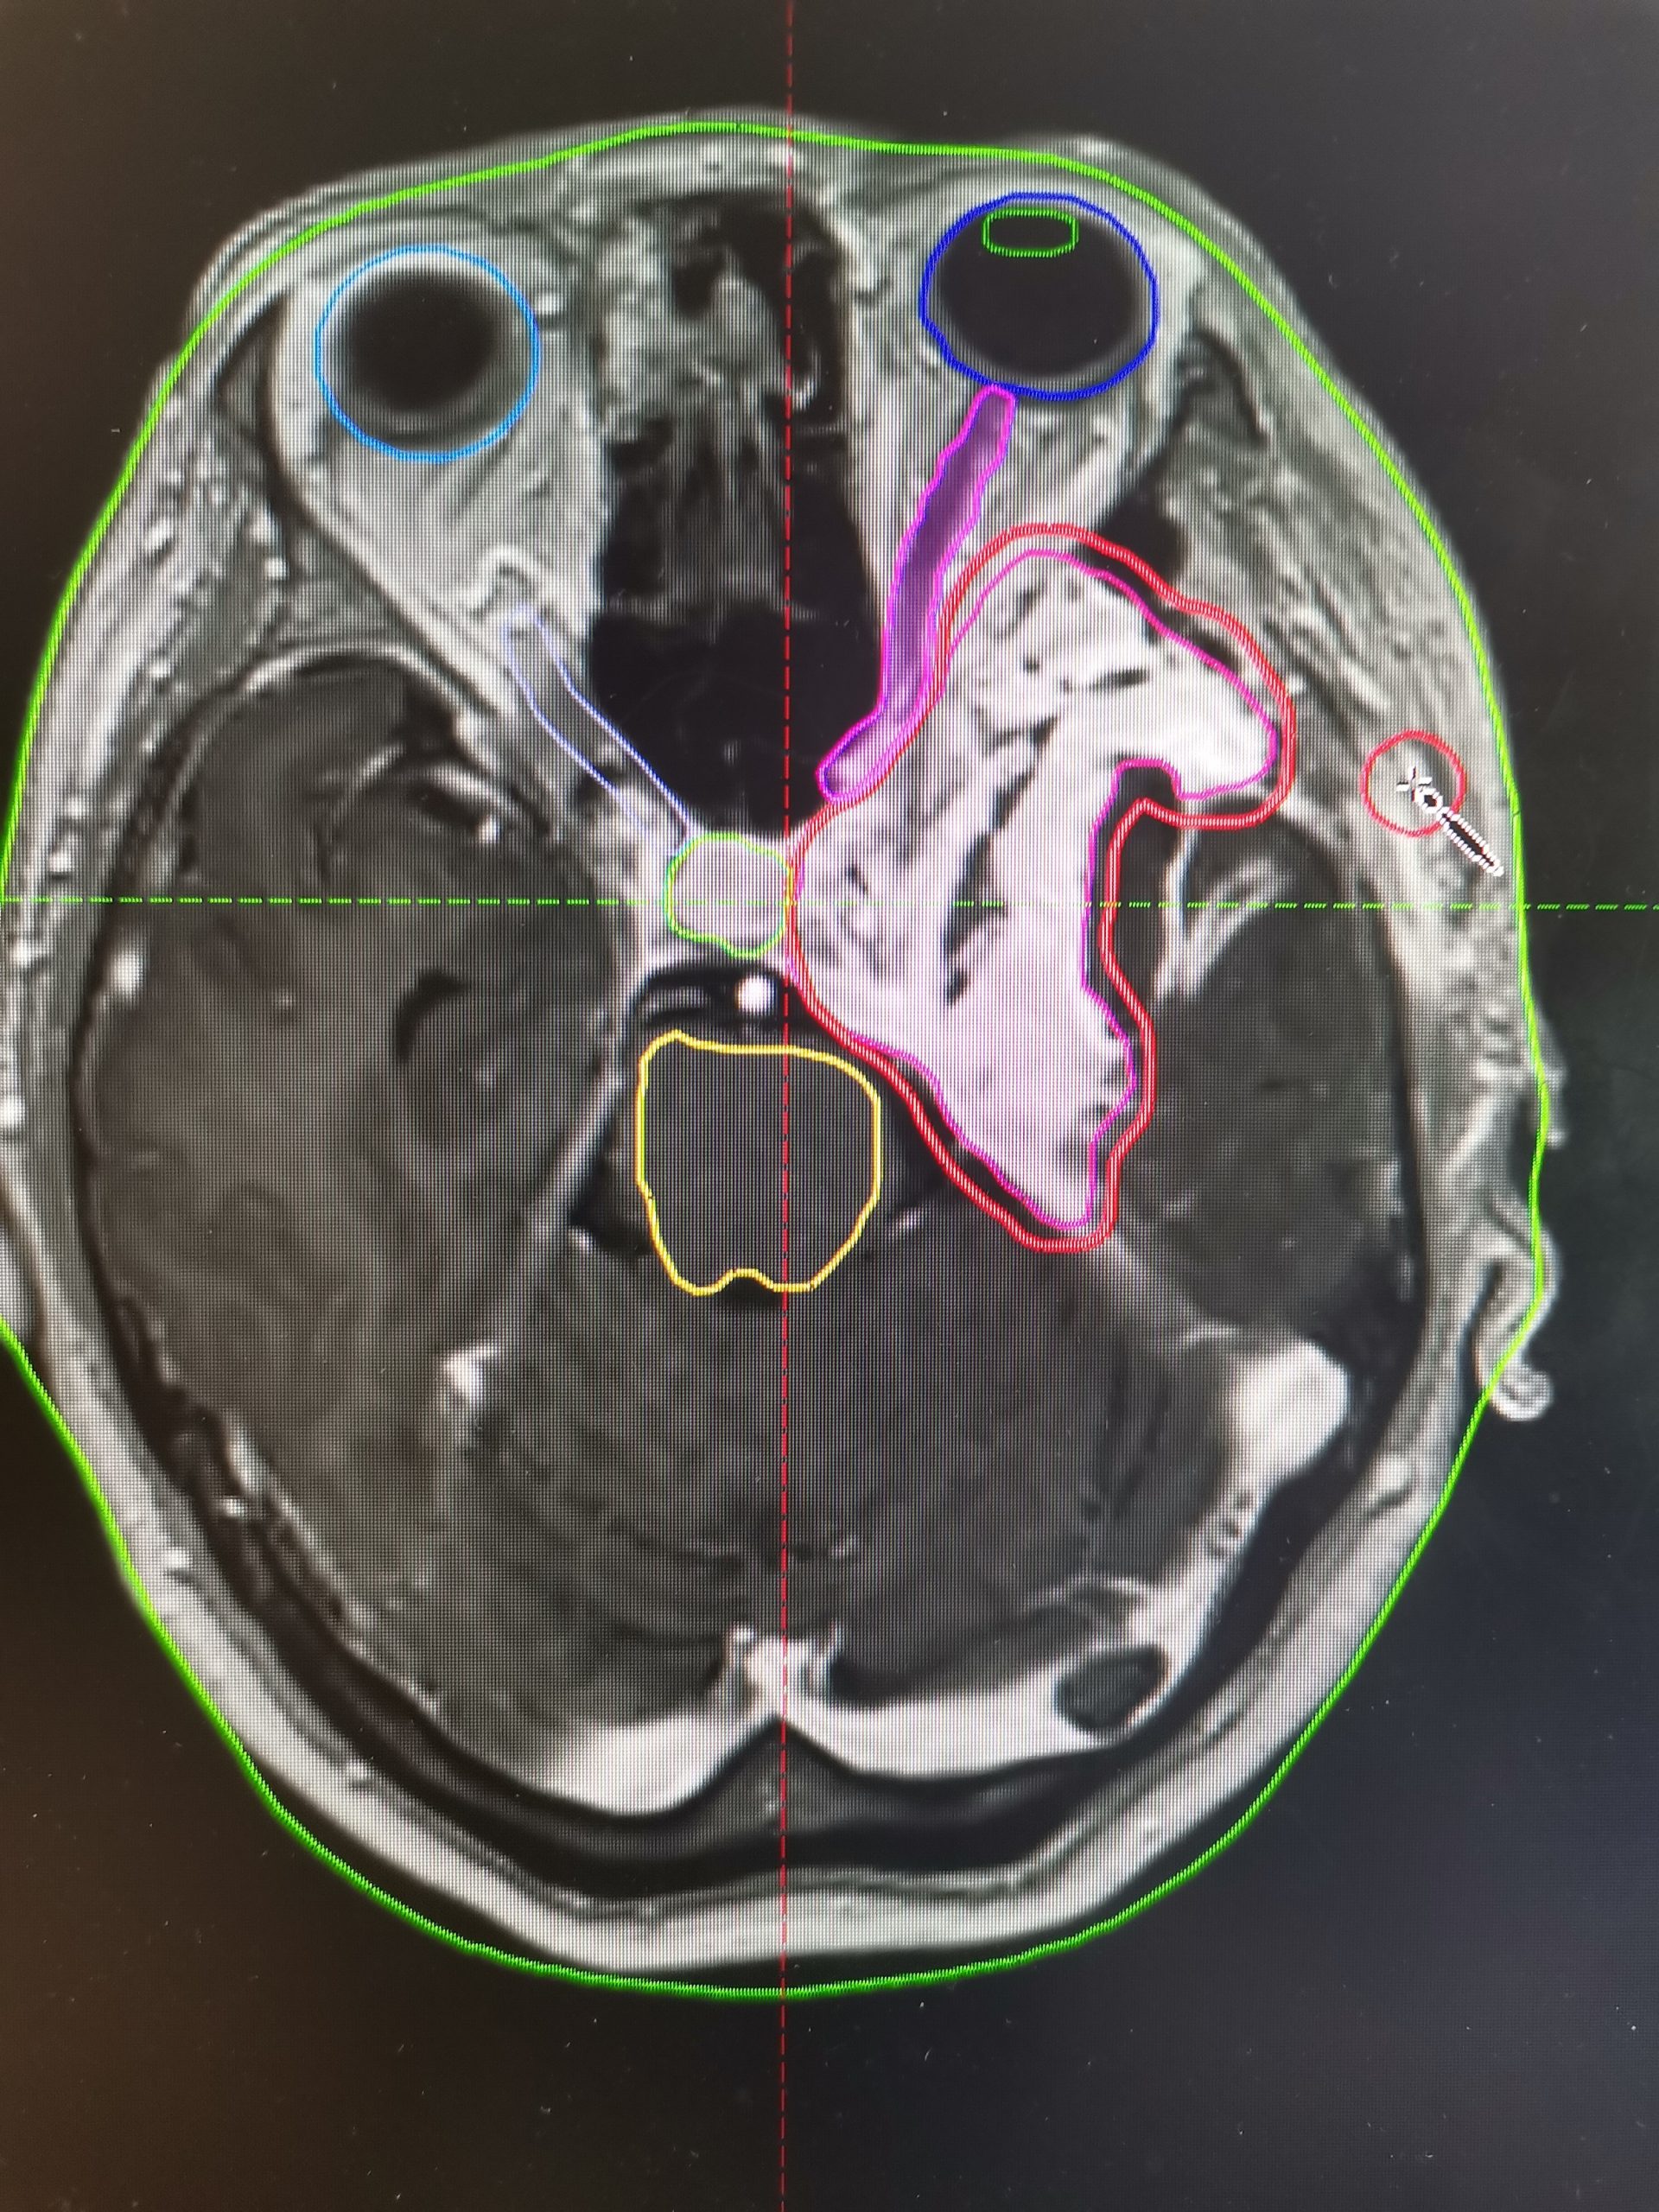

Особое значение современные технологии имеют при лечении опухолей головного мозга. Так, в ряде случаев, например при доброкачественных новообразованиях оболочек головного мозга, хирургическое вмешательство сопряжено с высоким риском утраты зрения и снижения слуха. В подобных клинических ситуациях единственным безопасным и радикальным методом лечения является высокотехнологичная лучевая терапия (фото).

В новом радиотерапевтическом корпусе Воронежского областного научно-клинического онкологического центра лучевая терапия проводится на линейном ускорителе Varian TrueBeam. Данный аппарат обеспечивает высокоточную доставку дозы непосредственно в опухолевый очаг при максимальной защите критически важных структур — органов зрения, слуха и головного мозга.

Применение современных методик лучевой терапии позволяет не только добиться высоких онкологических результатов, но и сохранить качество жизни пациентов, минимизировав риск таких осложнений, как снижение слуха, зрения и когнитивных функций.